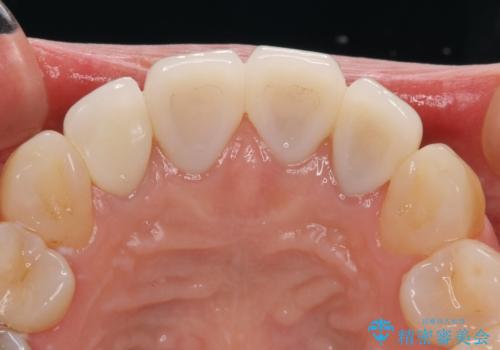

- 上顎4前歯に装着されているセラミッククラウンのうち、ひとつが欠けてしまったとのことで来院された患者様です。

土台となっている歯には問題がないため、周囲のセラミッククラウンと色調が合うように、オーダーメイドタイプのセラミッククラウンにて補綴治療を行うこととしました.

欠けてしまったセラミッククラウンはガラス系セラミッククラウンであったため、今回製作する歯は、強度の強いジルコニアセラミッククラウンとしました。

クラウンの種類は異なりますが、色調の適合したクラウンを装着することができました。